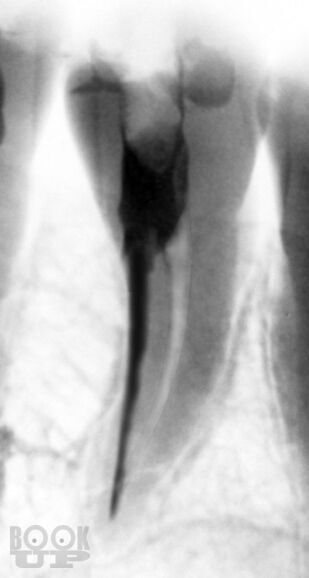

В учебно-методическом пособии представлены существующие классификации ошибок при лечении осложненного кариеса зубов. Проанализированы основные причины, приводящие к возникновению ошибок при диагностике, механической и медикаментозной обработке и обтурации корневых каналов. Рассмотрены методы предупреждения наиболее часто встречающихся осложнений эндодонтического лечения.